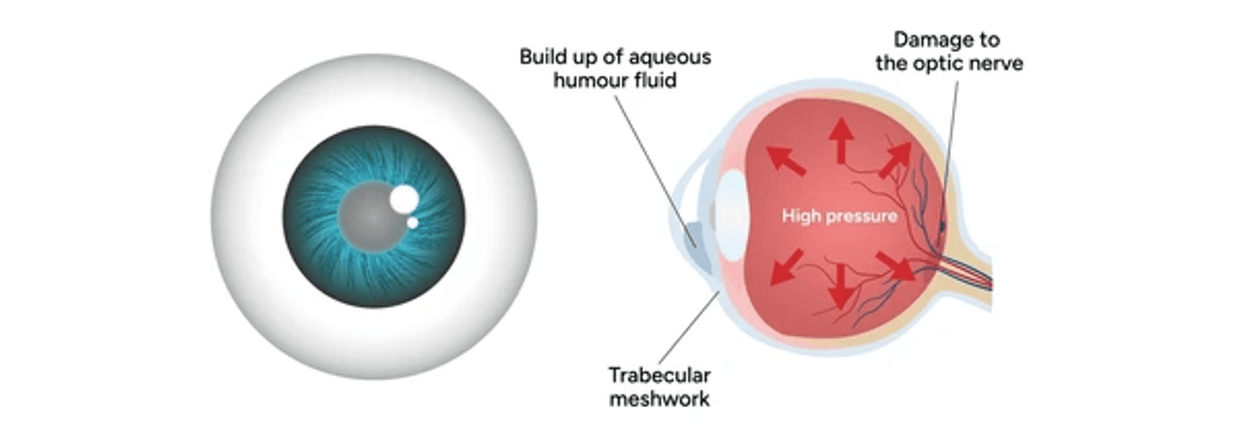

Le glaucome est une maladie oculaire caractérisée par des dommages progressifs du nerf optique, souvent associés à une élévation de la pression intraoculaire (PIO). Sans traitement, le glaucome peut conduire à une perte de la vision périphérique, puis à une cécité irréversible. Cette affection est l’une des principales causes de cécité dans le monde.

– Glaucome à angle ouvert : ce type est le plus fréquent. Il se développe lentement et ne présente souvent aucun symptôme au début. Dans le glaucome à angle ouvert, le liquide intraoculaire s’écoule moins efficacement, ce qui entraîne une augmentation de la PIO. Les patients ne remarquent généralement les effets que lorsqu’une partie importante de leur vision est déjà perdue.

– Glaucome à angle fermé : ce type est moins courant, mais constitue une urgence médicale. Il touche particulièrement les patients forts hypermétropes ou avec une cataracte avancée. Dans l’angle fermé, l’angle entre l’iris et la cornée est trop étroit, bloquant le drainage du liquide intraoculaire (humeur aqueuse) et provoquant une montée rapide de la PIO. Les symptômes incluent des douleurs oculaires sévères, des nausées, une vision floue, et des halos autour des lumières. Sans intervention immédiate, ce type de glaucome peut entraîner une perte rapide de la vision.